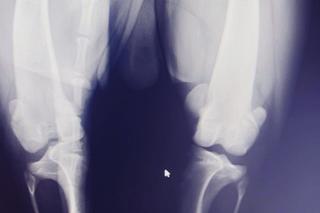

- Nogi zaraz odmówią mu posłuszeństwa. Ofiara pseudohodowli Chow Chow cierpi niemiłosiernie i prosi o serce. Łyse płaty skóry, wygięte nogi. Niczym trędowaty, bezsilny i obolały z ogromnym trudem porusza się, by móc zmienić pozycję. Żeby żyć - potrzebny tomograf, potrzebne zabiegi, potrzebna rehabilitacja. Dodatkowo problemy skórne oraz chora tarczyca. Dramat. Czas działa na niekorzyść Boryska. Dlatego pilnie potrzebne jest działanie- podają weterynarze.